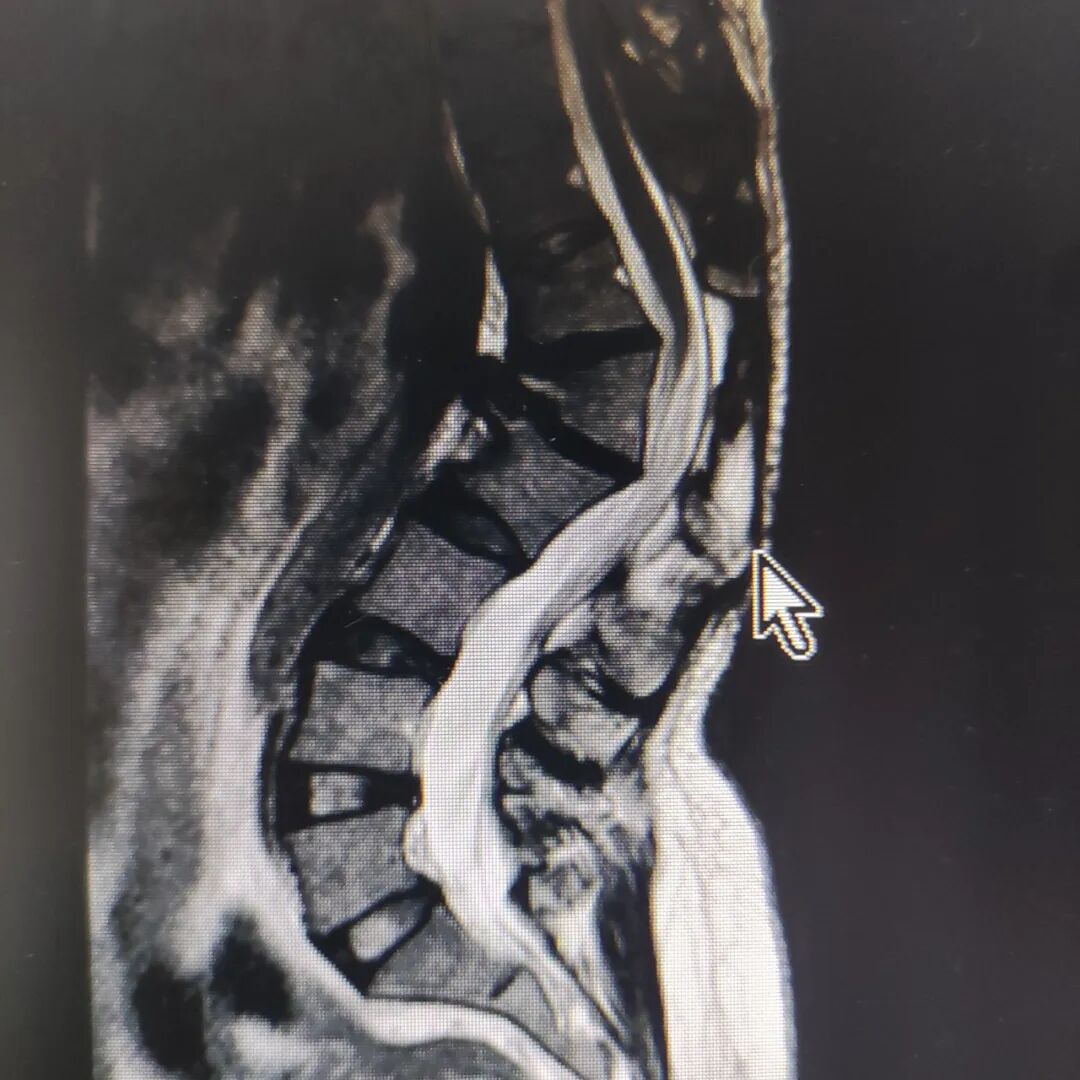

日前,安溪县中医院骨科成功实施我县首例脊柱截骨矫形术,这种畸形的矫正是一项操作复杂、技术要求极高的外科技术,一直以来都是是脊柱外科领域最具挑战性的课题。由于脊柱及其周围复杂而特殊的解剖特点,使得脊柱畸形矫形面临着极高的神经血管损伤风险,稍有不慎即会造成灾难性的后果。此次成功实施该手术,标志着我院骨科在脊柱领域再升新台阶。

近日,我院骨科收治一名特殊的病人。该病人因十余年前外伤致腰椎骨折后未系统诊治,今出现双下肢麻木,疼痛难忍,甚至行走困难。经过拍片及相关辅助检查后,诊断为:脊柱后凸畸形。

此次手术我院采用了国内外先进的VCD脊柱截骨矫形技术尽量减少对脊髓的干扰,且术中使用了一体式C臂机、脊髓电生理监护仪等为患者保驾护航,确保手术的成功。